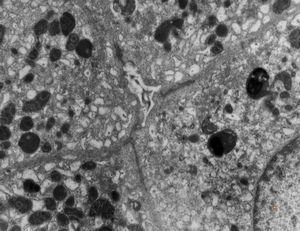

M,19y. | normal hepatocyte